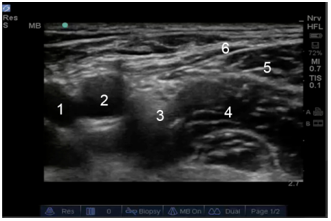

1. Fascia Lata

2. Fascia Iliaca

3. Femoral Vein

4. Femoral Artery

5. Femoral Nerve

6. Iliacus Muscle